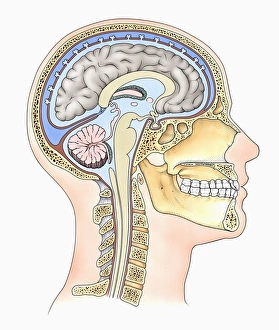

The central nervous system, the intricate network that governs our every thought and movement, is a marvel of complexity. From the delicate cerebellum tissue to the detailed light micrograph capturing its essence, we are reminded of its importance in maintaining balance and coordination. Anatomy comes alive as we explore the human brain from an inferior view. The intricacy of brain fibers is revealed through DTI MRI scans like C017/7099 and C017/7035, showcasing their vital role in transmitting information throughout this extraordinary organ. Artistic renderings bring us closer to understanding the medulla oblongata's significance within the brain. Its portrayal in various artworks allows us to appreciate how it controls essential functions such as breathing and heart rate. As we delve deeper into studying the central nervous system, models of the human brain provide invaluable insights into its structure and organization. Lateral views reveal countless regions responsible for cognition, emotion regulation, sensory perception, and motor control. Microscope slides offer glimpses into nerve cells' intricate architecture—a testament to their ability to transmit electrical signals at lightning speed. Meanwhile, glial stem cell cultures captured under a light microscope remind us of their crucial role in supporting neuronal function. Finally, artistic representations unveil the limbic system's enigmatic nature—an interconnected web responsible for emotions and memory formation. These captivating artworks allow us to visualize this complex network within our brains. Exploring these hints provides a glimpse into the awe-inspiring world of our central nervous system—the very foundation upon which our thoughts, actions, memories reside—reminding us just how remarkable our brains truly are.